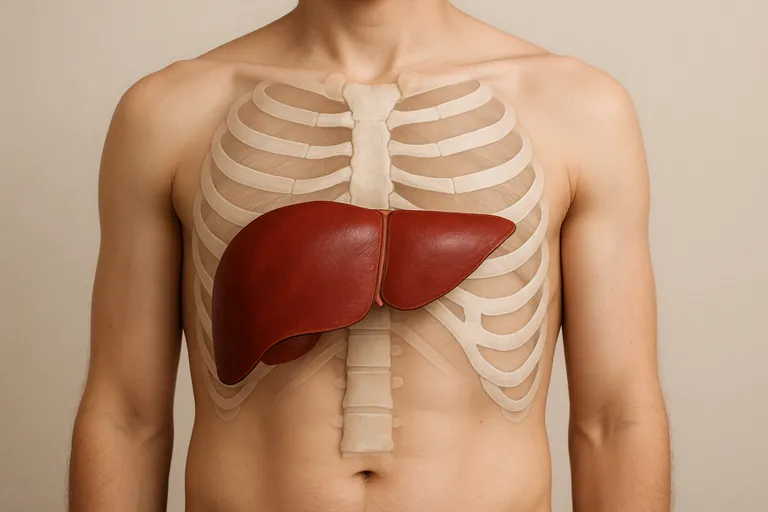

Waar zit je lever precies?

Je lever ligt rechtsboven in je buik, direct onder de rechterribben en tegen het middenrif aan. Het grootste deel bevindt zich aan de rechterkant, maar een dunne linkerkwab steekt over de middellijn naar links, tot net achter je borstbeen. De bovenkant volgt de koepel van het middenrif en beweegt mee met elke ademhaling; bij een diepe inademing zakt de lever 2 à 3 centimeter, waardoor de onderrand net onder de ribben voelbaar kan worden. Het is een groot, stevig orgaan van ongeveer anderhalve kilo dat veel ruimte inneemt in de rechterbovenbuik. Aan de onderkant ligt je galblaas tegen de rechterleverkwab; links ervan liggen je maag en iets lager je darmen, terwijl achter de lever de rechternier en grote bloedvaten lopen.

Dankzij de ribben is de lever goed beschermd en kun je hem normaal gesproken niet zien of voelen. Wil je de plek globaal vinden, leg dan je hand plat onder je rechterribbenboog; daar, iets richting het midden, zit de onderrand. Bij kinderen en slanke volwassenen is die rand soms iets makkelijker te voelen. Houd er rekening mee dat houding, lichaamstype, zwangerschap en een volle maag de positie een beetje kunnen laten variëren, maar je lever blijft hoofdzakelijk rechts. Alleen in zeldzame gevallen, zoals bij situs inversus (een omgekeerde orgaanligging), zit je lever links.

Ligging en begrenzing: rechterbovenbuik en een stukje over de middellijn

Je lever ligt hoofdzakelijk in je rechterbovenbuik, direct onder de rechterribben en tegen het middenrif. De grootste massa zit rechts, maar de linkerkwab steekt als een platte tong over de middellijn naar links, tot net achter je borstbeen. Boven grenst de lever aan het middenrif en de onderrand volgt de ribbenboog; bij diep inademen kan die onderrand heel even onder de ribben voelbaar zijn.

Aan de voorkant zit een bindweefselband die de lever aan je buikwand verankert rond de middellijn, wat de scheiding tussen rechts en links markeert. Achter de lever lopen grote bloedvaten en ligt de rechternier, links ervan zitten je maag en hoger je slokdarm. Door de ribben is je lever goed beschermd, waardoor je hem normaal niet ziet of voelt.